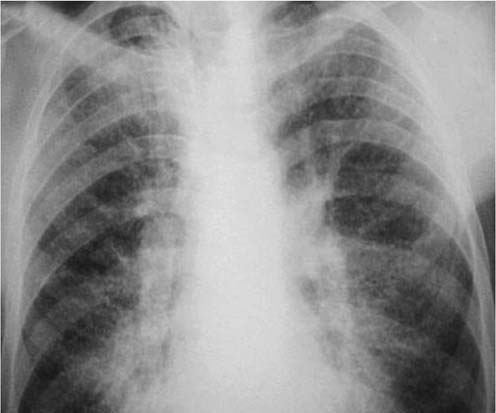

На рентгенограммах у больных АП определяют мелкоочаговые (мелкоточечные) затемнения, имеющие тенденцию к слиянию.

Рис. 2. Обзорная рентгенограмма органов грудной клетки больного с альвеолярным протеинозом.

Картина двустороннего неоднородного ''пятнистого" затемнения по форме напоминающего "крылья летучей мыши" Изменения чаще носят симметричный характер. Рентгенологическая картина напоминает альвеолярный отек легкого.